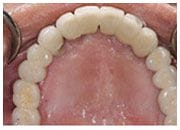

上顎治療

治療前

治療後